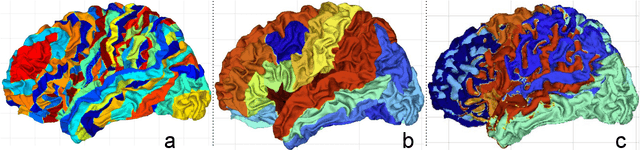

Abstract:Cortical surface parcellation is a fundamental task in both basic neuroscience research and clinical applications, enabling more accurate mapping of brain regions. Model-based and learning-based approaches for automated parcellation alleviate the need for manual labeling. Despite the advancement in parcellation performance, learning-based methods shift away from registration and atlas propagation without exploring the reason for the improvement compared to traditional methods. In this study, we present JParc, a joint cortical registration and parcellation framework, that outperforms existing state-of-the-art parcellation methods. In rigorous experiments, we demonstrate that the enhanced performance of JParc is primarily attributable to accurate cortical registration and a learned parcellation atlas. By leveraging a shallow subnetwork to fine-tune the propagated atlas labels, JParc achieves a Dice score greater than 90% on the Mindboggle dataset, using only basic geometric features (sulcal depth, curvature) that describe cortical folding patterns. The superior accuracy of JParc can significantly increase the statistical power in brain mapping studies as well as support applications in surgical planning and many other downstream neuroscientific and clinical tasks.

Abstract:The varying cortical geometry of the brain creates numerous challenges for its analysis. Recent developments have enabled learning surface data directly across multiple brain surfaces via graph convolutions on cortical data. However, current graph learning algorithms do fail when brain surface data are misaligned across subjects, thereby affecting their ability to deal with data from multiple domains. Adversarial training is widely used for domain adaptation to improve the segmentation performance across domains. In this paper, adversarial training is exploited to learn surface data across inconsistent graph alignments. This novel approach comprises a segmentator that uses a set of graph convolution layers to enable parcellation directly across brain surfaces in a source domain, and a discriminator that predicts a graph domain from segmentations. More precisely, the proposed adversarial network learns to generalize a parcellation across both, source and target domains. We demonstrate an 8% mean improvement in performance over a non-adversarial training strategy applied on multiple target domains extracted from MindBoggle, the largest publicly available manually-labeled brain surface dataset.